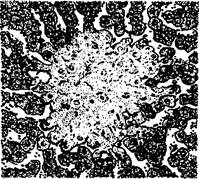

Некротический фокус в печени теленка при сальмонеллезе

Сальмонеллезная гранулема в печени теленка

Гранулемы (паратифозные узелки) имеют вид очажков размножающихся ретикулоэндотелиальных элементов, расположенных по ходу капилляров. Клетки гранулем со светлыми крупными ядрами обладают способностью к фагоцитозу. Кроме печени и селезенки паратифозные узелки отмечают также в почках, лимфатических узлах, костном мозге. В печени и реже в других органах можно наблюдать образование очаговых эндофлебитов, но они не патогномоничны для сальмонеллеза.